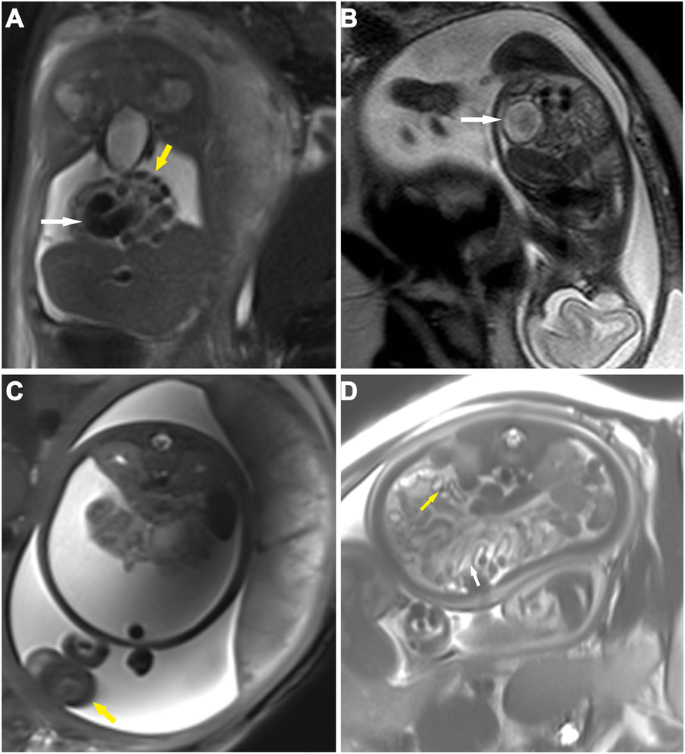

The imaging findings on both ultrasound and MRI are summarized in Table 1, and representative imaging findings are shown in Fig. 1 (ascites, gathered bowel loops, bowel dilatation, meconium pseudocysts, peritoneal calcification and hydroceles) and Fig. 2d (micro-colorectum). Ascites and bowel dilatation were two of the most common findings on both ultrasound and MRI. Distended bowel loops (27:4 on MRI or ultrasound), micro-colorectum (13:1), meconium pseudocysts (10:3) and hydroceles (13:4) were more likely to be depicted by MRI than by ultrasound. Of all 35 patients, 26 received surgical management. The intraoperative findings corresponded to the findings on MRI scanning. Atresia and perforation, two of the main causes of MP, were visualized in 22 and 12 infants, respectively.

Fetal MRI findings of meconium peritonitis. a A coronal 3.0-T fat-suppression T2-weighted image (HASTE, TR = 15,000 ms, TE = 91 ms) reveals a moderate amount of ascites (a low-intensity signal) in the peritoneal cavity, compacted bowel loops (yellow arrow) and dilated bowels (white arrow) in a 30-week-old fetus with meconium peritonitis (MP). b A sagittal 1.5-T fetal T2-weighted image (TR = 15,000 ms, TE = 120 ms) shows mild ascites among bowel loops and a cyst (a 3.2 × 2.4 × 3.2 cm round foci with mix signal inside, white arrow) in a 24-week-old fetus with MP. c A transverse 3.0-T HASTE-FS image (TR = 15,000 ms, TE = 91 ms) indicates a high mount of ascites, gathered bowel loops (white arrow) and enlargement of the left scrotum (yellow arrow) in a 37-week-old fetus with MP. d A transverse 3.0-T fat-suppression T2-weighted image (HASTE, TR = 15,000 ms, TE = 91 ms) indicates gathered bowel loops (white arrow) and calcification spots (multiple small focuses or small nodules with low T2-weighted imaging signal, yellow arrow) in a 38-week-old fetus with MP

To investigate the value of fetal MRI findings for predicting the need for surgical intervention, we divided all infants into an operative group and an observation group according to whether they received a postpartum operation, and we performed Fisher’s exact probability tests to analyze the correlations (Table 2). The presence of bowel dilatation (14/26, p = 0.048) and micro-colorectum (13/26, p = 0.013) seemed to be associated with the need for postpartum surgical intervention (Fig. 2). Of the 9 infants with nonsurgical interventions after delivery, 8 infants had ascites or/and distended bowel loops. There was only one infant with MRI signs of peritoneal calcifications or meconium pseudocysts who received conservative treatment (Fig. 3). Although the number of infants with meconium pseudocysts or peritoneal calcifications was not significantly different between the two groups, surgical intervention was considered when the MRI also revealed the presence of other findings other than ascites or distended bowel loops. Infants with hydrops in an enlarged scrotum did not need to undergo surgical treatment because of the self-healing capabilities of the body.